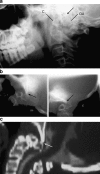

Background: The embryology of the bony craniovertebral junction (CVJ) is reviewed with the purpose of explaining the genesis and unusual configurations of the numerous congenital malformations in this region. Functionally, the bony CVJ can be divided into a central pillar consisting of the basiocciput and dental pivot and a two-tiered ring revolving round the central pivot, comprising the foramen magnum rim and occipital condyles above and the atlantal ring below. Embryologically, the central pillar and the surrounding rings descend from different primordia, and accordingly, developmental anomalies at the CVJ can also be segregated into those affecting the central pillar and those affecting the surrounding rings, respectively.

Discussion: A logical classification of this seemingly unwieldy group of malformations is thus possible based on their ontogenetic lineage, morbid anatomy, and clinical relevance. Representative examples of the main constituents of this classification scheme are given, and their surgical treatments are selectively discussed.